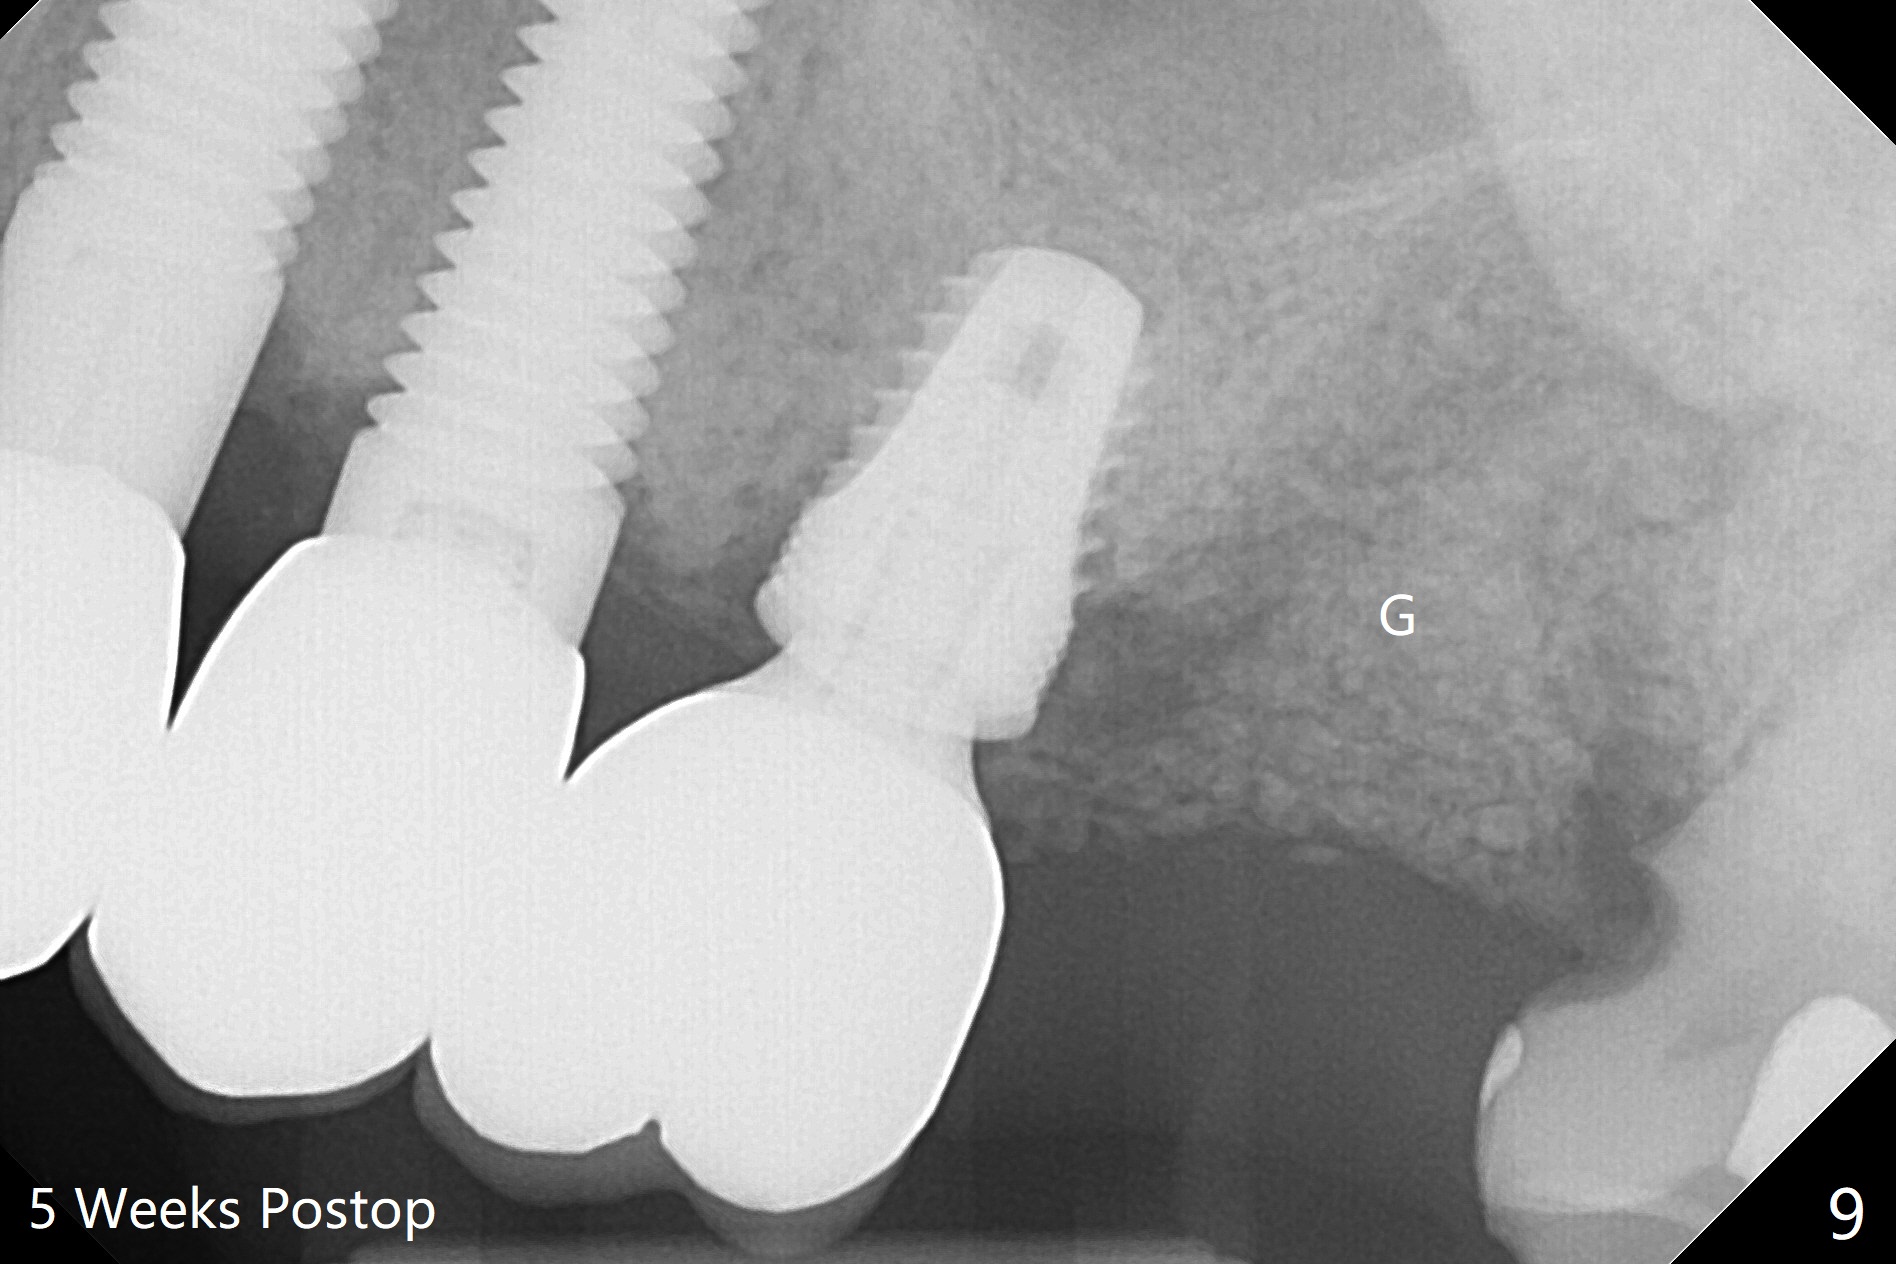

The 7x14 mm implant at #15 of a 89-year-old man is found to be loose ~ 1 year post cementation (Fig.1). After implant removal and debridement, bone graft is placed (Fig.2 G); the mesiocervical caries of the 3rd molar is removed, but not filled (*). With collagen membrane fixed with Chromic gut suture (Fig.3), setting acrylic is applied in the edentulous area, including the mesiocervical cavitation of the 3rd molar (Fig.4) for further retention. Bone graft gets lost following socket preservation at #31 with periodontal dressing. When the bone graft matures, a new implant (Fig.6 green) will get primary stability from the native bone, i.e., coronal to the sinus floor (Fig.5 F). The acrylic dressing (Fig.7 A) with a portion locking to the undercut of the neighboring crown (*) remains in place 5 weeks postop. When the dressing is cut off, the bone graft is exposed with odor (Fig.8,9 *). Periodontal dressing is applied. The distolingual portion of it gets lost due to brushing a day later. When he returns, the dressing is removed (Fig.10). It appears that the growing in gingival margin is pushing the bone graft out. A moment later after just a few rounds of swallowing, more graft is lost (Fig.11). We would love to leave the wound open, but the senior citizen complains of air leaking and requests reapplication of periodontal dressing. The bone graft is almost gone when the 2nd periodontal dressing is removed nearly 2 months postop (Fig.12). The tooth sensitivity disappears when MO caries is taken care of. The socket has a dimple 5 months postop (Fig.13), although it is filled with bone graft (Fig.14). Due to low bone density (~500 HU), sinus lift is required for implant stability with PRF (Fig.15). In fact the lab chooses not to do sinus lift.